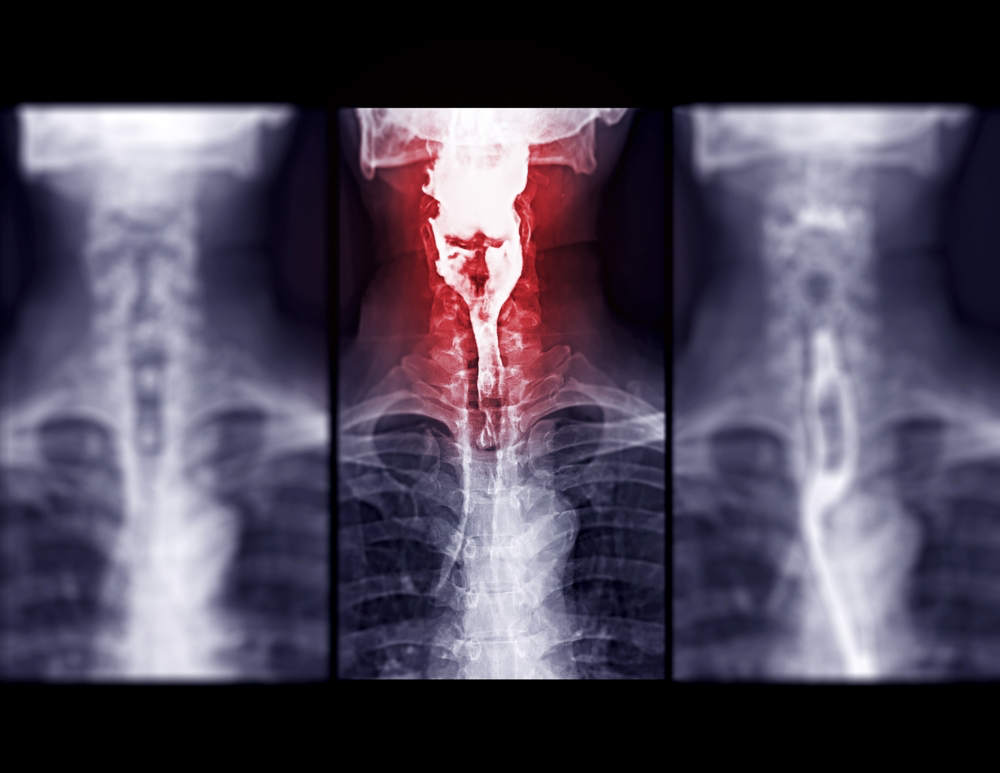

What are x-rays?

Since their discovery in 1895 by the German physicist Wilhelm Roentgen, X-rays have played a major role in helping physicians diagnose and treat disease. X-rays are high-energy electro-magnetic waves created within an x-ray tube.

They are highly penetrating, and in combination with computer imaging plates, provide images of various internal organs and structures.

Your physician and the radiologist combine to provide you with the test best suited to your particular situation. While all radiation exposure carries some risk, the benefits of diagnosing your condition far outweigh these risks.

However, due to these risks, X-ray examinations are carried out by trained, licensed personnel and interpreted by physicians (radiologists) who are specially trained in the imaging sciences.

Pueblo radiology x-ray services: